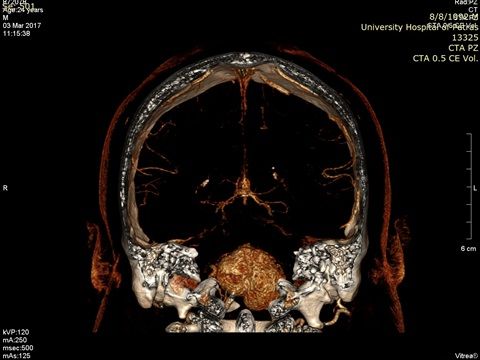

Preoperative large brain meningioma.

Neurosurgical practice includes diagnosis (by stereotactic biopsy) and treatment by removal of brain tumours (gliomas, meningiomas, metastases, etc.). Surgical intervention is performed in a state-of-the-art manner using neuroplanning and brain mapping. Preoperatively in many cases we follow a special protocol that includes CT angiography scanning and embolization of the tumors so that surgical removal is possible.